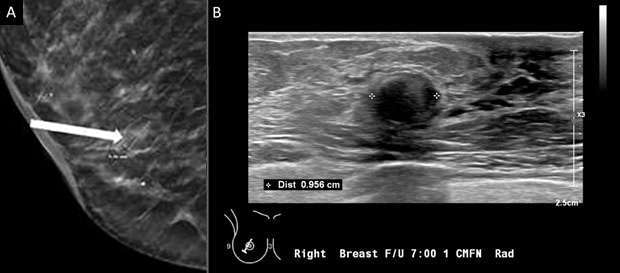

2. Round: a round mass (Figure 2) is spherical, ball-shaped, circular, or globular in shape.

Mammography: Masses Figure 2

Figure 2: A) On Mammogram rim-calcified round mass was noted in the right breast at 7 o'clock, lower outer quadrant located 1 centimeter from the nipple (white arrow). B) Ultrasound demonstrates a round mass with peripheral hyperechogenicity measuring 10 x 7 x 10 mm in the right breast at 7 o'clock located 1 centimeter from the nipple, favoring fat necrosis. BI-RADS Category: 2.